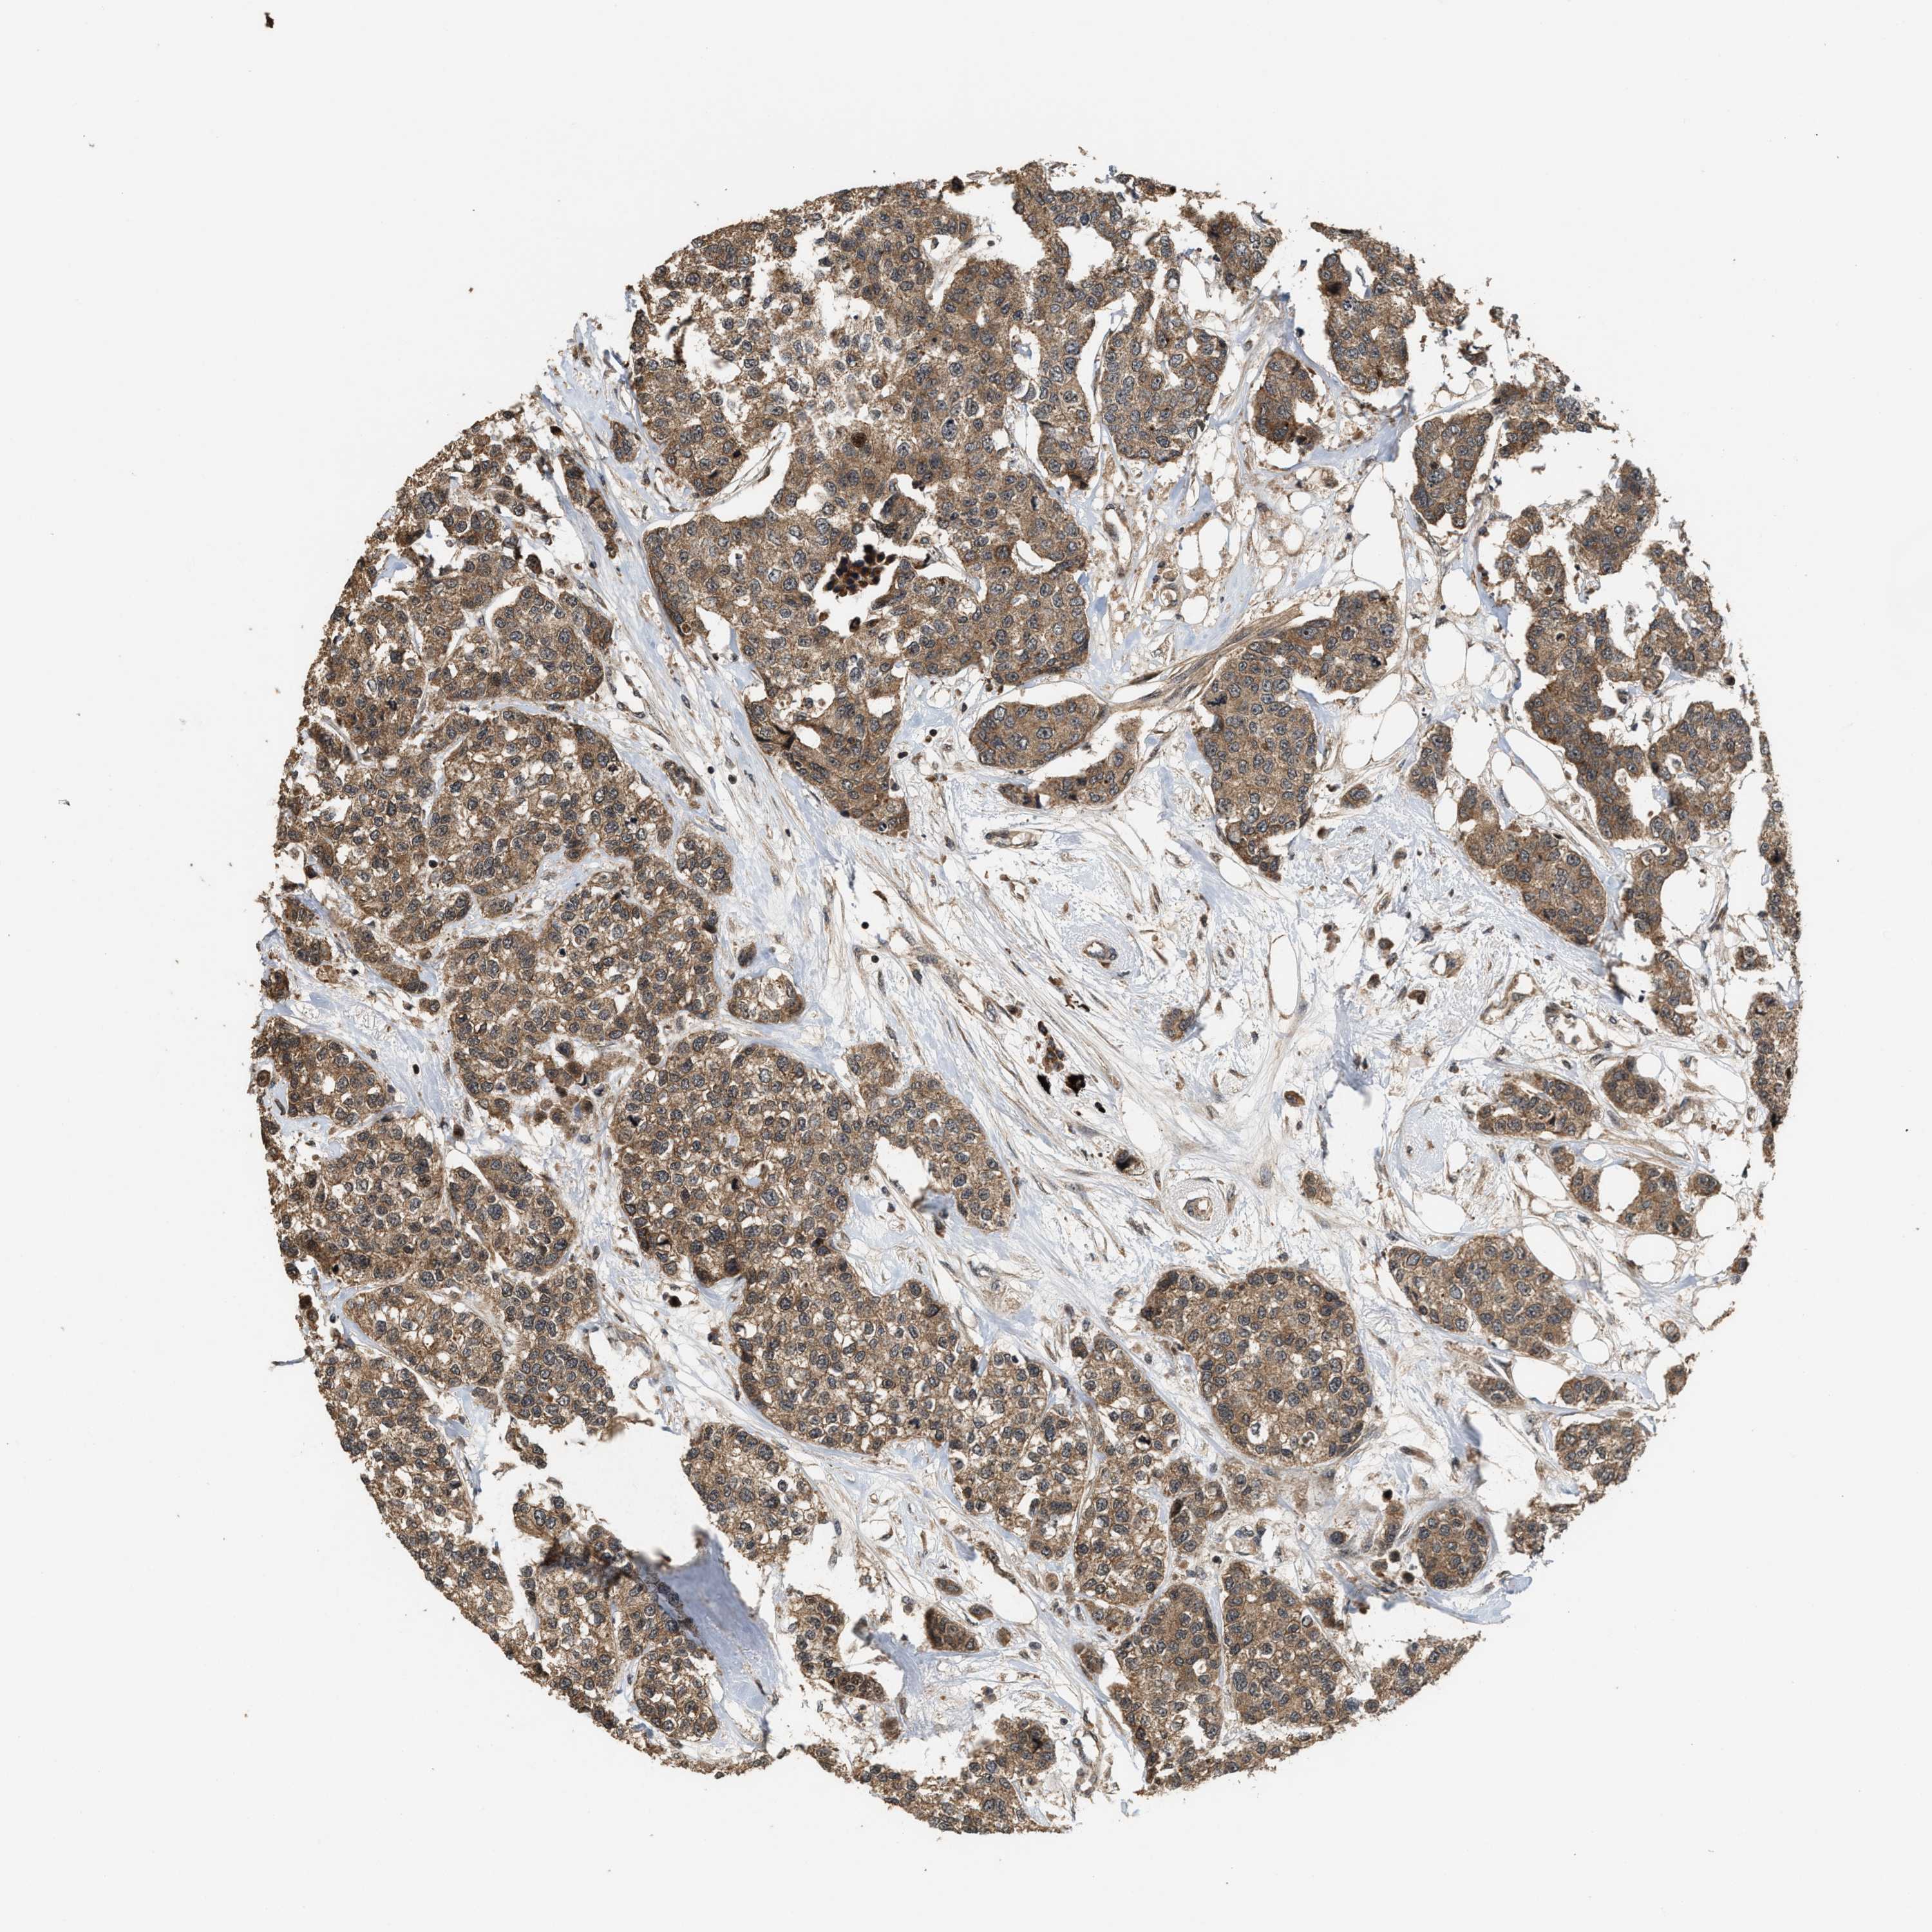

BRCA TCGA BRCA VALIDATION PROTEIN EXPRESSION

ANTIBODIES

AND

VALIDATION